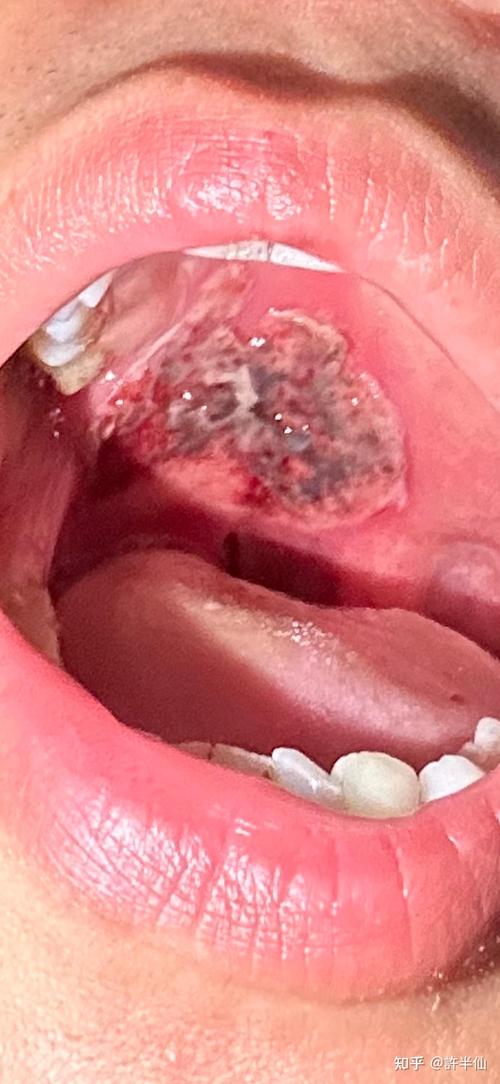

化疗后口腔大面积溃疡怎么办?

非常理解您此刻的痛苦和焦虑,化疗后出现大面积口腔溃疡,是化疗非常常见且令人痛苦的副作用,医学上称为口腔黏膜炎,它不仅影响进食、说话,还会带来剧烈疼痛,甚至增加感染风险。

(图片来源网络,侵删)

- 溃疡范围扩大或数量增多:溃疡面积很大,或布满整个口腔。

- 发现白色或黄色斑点/斑块:这可能是念珠菌(真菌)感染的迹象,需要抗真菌治疗。